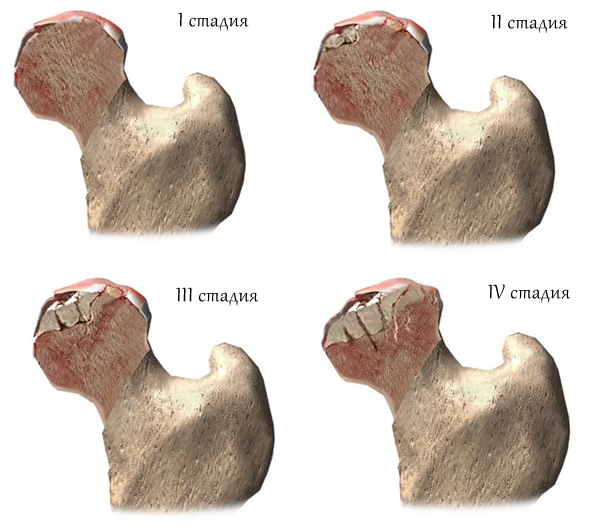

Применяются следующие методы лечения:

- На первой стадии заболевания иногда достаточно гипсовой повязки. Однако чаще всего в шейку и головку бедра устанавливают штифт для фиксации отломков или используют спицы и тонкие гвозди, которые удаляются после закрытия зоны роста.

- На второй стадии (хроническая форма с смещением эпифиза назад менее чем на 30°) применяются спицы и трансплантаты.

- На третьей стадии (при смещении головки более чем на 30°) необходимо провести остеотомию (удаление дефекта путем искусственного рассечения костной ткани). Отломки удаляются, а фрагменты костей фиксируются спицами, винтами или пластинами. Операция выполняется поэтапно: сначала создается соединение между эпифизом и метафизом, а после закрытия ростковой зоны проводится коррекционная остеотомия.

- На четвертой стадии (полное смещение эпифиза) применяется закрытая репозиция (совмещение отломков кости без повреждения тканей) с последующим вытяжением скелета на срок около одного месяца. Затем выполняется остеосинтез головки и шейки бедра с использованием спиц и костного трансплантата. Репозиция может осуществляться как вручную хирургом, так и с помощью специального аппарата.

- При пятой стадии заболевания (закрыта ростковая зона, смещение эпифиза превышает 30°, имеются остаточные деформации) проводится коррекционная остеотомия, но чаще ограничиваются наложением гипсовой повязки.